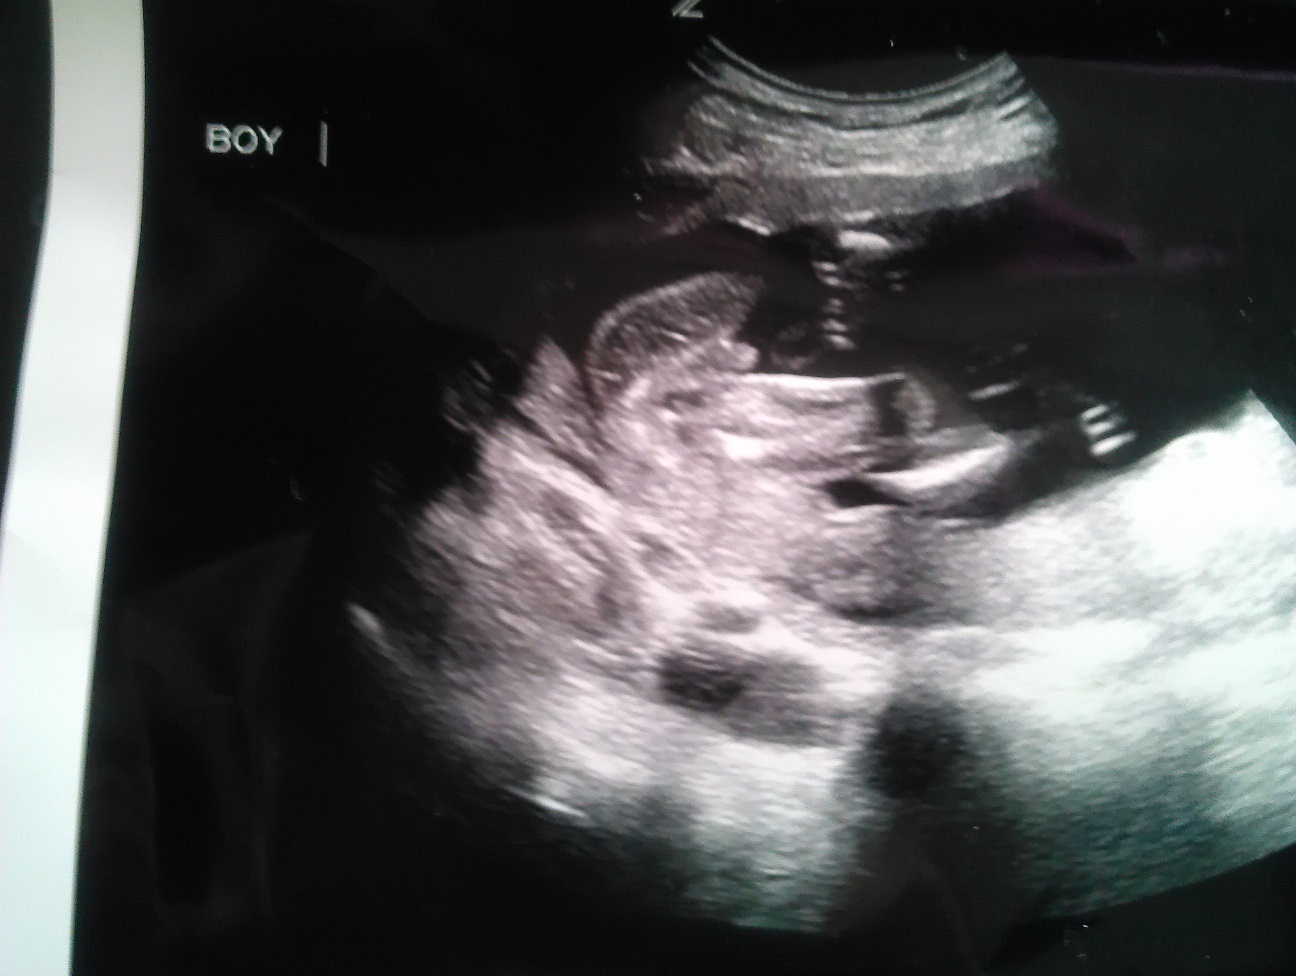

This is my baby at 19w2d. I know he's a boy. I just need to hear a resounding, "Yes, he's a boy!" With ds2 I could clearly see his scrotum. I'm sure his are just hiding or maybe I just don't know what I'm looking at. lol! I want to nip the denial stage in the bud. TIA!!!

Attachment 10932